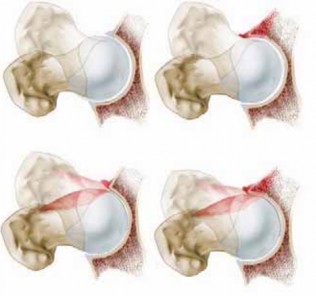

A library of advanced orthopedic surgical techniques, providing step-by-step guidance for complex musculoskeletal procedures.